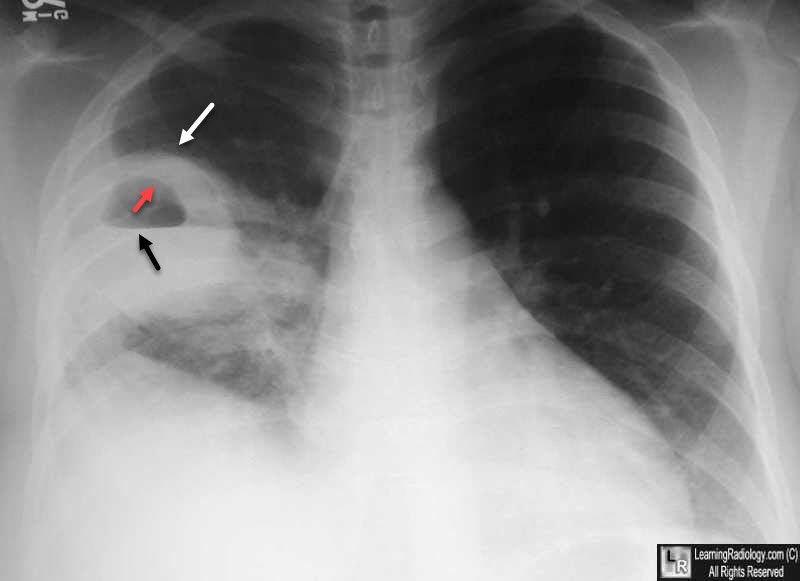

- X-ray chest (P/A view): Showing a well circumscribed area of dense opacity with cavitation & air fluid level.